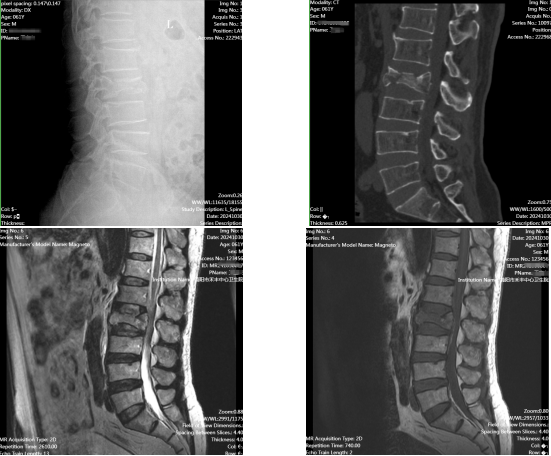

简阳市禾丰中心卫生院(简阳市第二人民医院)骨科与麻醉手术室团队在罗德军博士的带领下,共同书写了医院手术史的新篇章。近期,他们成功完成了医院首例复杂且高难度的腰椎爆裂性骨折伴椎管狭窄患者的手术治疗,该手术方式为:经后路腰椎爆裂性骨折切开复位钉棒系统内固定术与椎管扩大减压术,这不仅展示了医院在该片区骨科领域的卓越技术实力,更为患者带来了福音。

罗德军博士带领总院下沉骨科专家陈帅主治医师、麻醉专家尚子淇主治医师及本院骨科团队通过术前讨论制定了详细稳妥的手术及麻醉方案,更是凭借深厚的专业知识和丰富的临床经验,在全身麻醉下精准地实施了钉棒系统内固定术,有效稳定了患者受损的腰椎,为后续恢复奠定了坚实基础。同时,通过椎管扩大减压术,成功解除了骨折碎片对脊髓和神经根的压迫,有效预防了潜在的神经损伤风险。